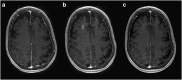

Magnetic resonance-guided focused ultrasound in combination with intravenously injected microbubbles has been shown to transiently open the blood-brain barrier, and reduce beta-amyloid and tau pathology in animal models of Alzheimer's disease. Here, we used focused ultrasound to open the blood-brain barrier in five patients with early to moderate Alzheimer's disease in a phase I safety trial. In all patients, the blood-brain barrier within the target volume was safely, reversibly, and repeatedly opened. Opening the blood-brain barrier did not result in serious clinical or radiographic adverse events, as well as no clinically significant worsening on cognitive scores at three months compared to baseline. Beta-amyloid levels were measured before treatment using [18F]-florbetaben PET to confirm amyloid deposition at the target site. Exploratory analysis suggested no group-wise changes in amyloid post-sonication. The results of this safety and feasibility study support the continued investigation of focused ultrasound as a potential novel treatment and delivery strategy for patients with Alzheimer's disease.